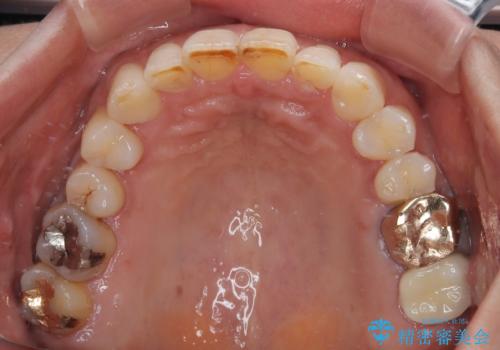

デコボコの歯とむし歯 インビザライン矯正治療とむし歯治療

- 奥歯が咬めないくらいに痛いとのことで来院された患者様です。

痛みの強い歯は、歯髄組織が強い炎症を起こしており、神経を取り除く必要であったため、速やかに根管治療を行いました。

その後、オールセラミッククラウンにて補綴治療を行う予定でしたが、処置した歯以外にも治療が必要と思われる歯があったり、デコボコした歯列も気になるとのことで、患者様希望によりインビザラインにてマウスピース矯正を行うこととしました。

まずは矯正治療前に必要なむし歯処置を行い、その後矯正治療を行ってから、最後にオールセラミッククラウンなどで補綴治療を行うこととしました。

咬合力が非常に強く、全体的に歯が擦り減っている状態であったので、理想的な咬み合わせを達成することは難しく、また咬合力が強い方のマウスピース矯正は、思い通りに動かないことがあるため、ワイヤー矯正の方が望ましいように思えました。